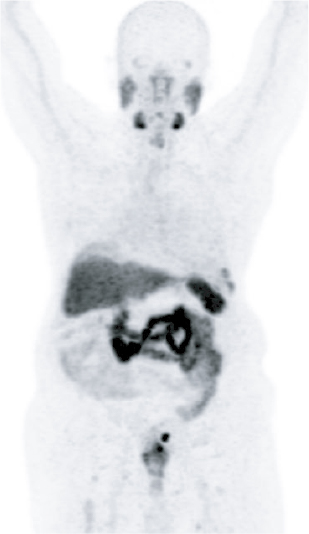

Precision imaging using advanced modalities such as PSMA PET-CT

Accurate identification of disease spread

Ability to target cancer cells at a molecular level

Real-time monitoring of treatment response

Cancer widely spread to lungs, bones, and lymph nodes

Resolution of lung metastases

No active lymph node involvement

Significant reduction in bone lesions